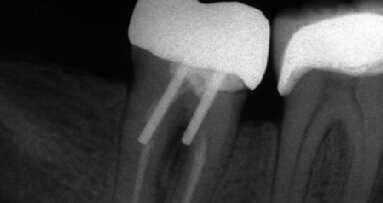

Během stomatologických výkonů vytvářejí rotační a jiné nástroje částice zvané aerosoly (obr. 5). Ty mohou obsahovat zbytky dentinu a skloviny, dentinové smear layer nebo úlomky kompozitu, provizorního cementu nebo past. Do vzduchu se uvolňují také bioaerosoly obsahující sliny, krev a další biologické tekutiny. Vysoká míra kontaminace bioaerosoly se vyskytuje na brýlích a maskách stomatologů a jejich asistentů.